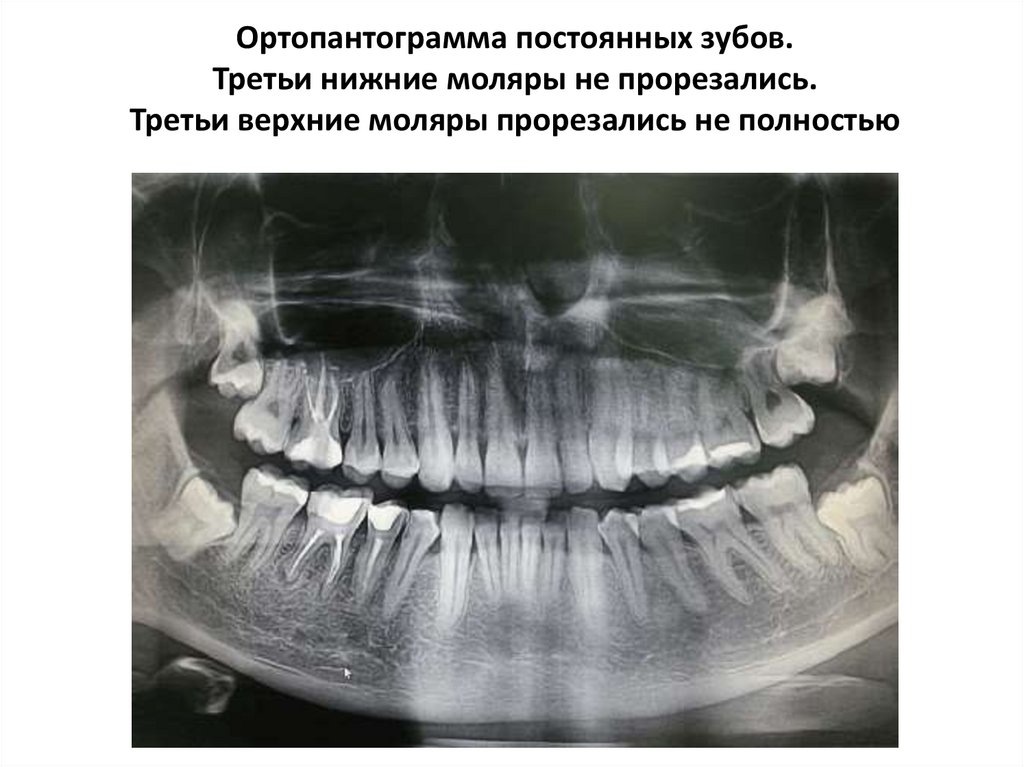

Ортопантограмма постоянных зубов.

Третьи нижние моляры не прорезались.

Третьи верхние моляры прорезались не полностью